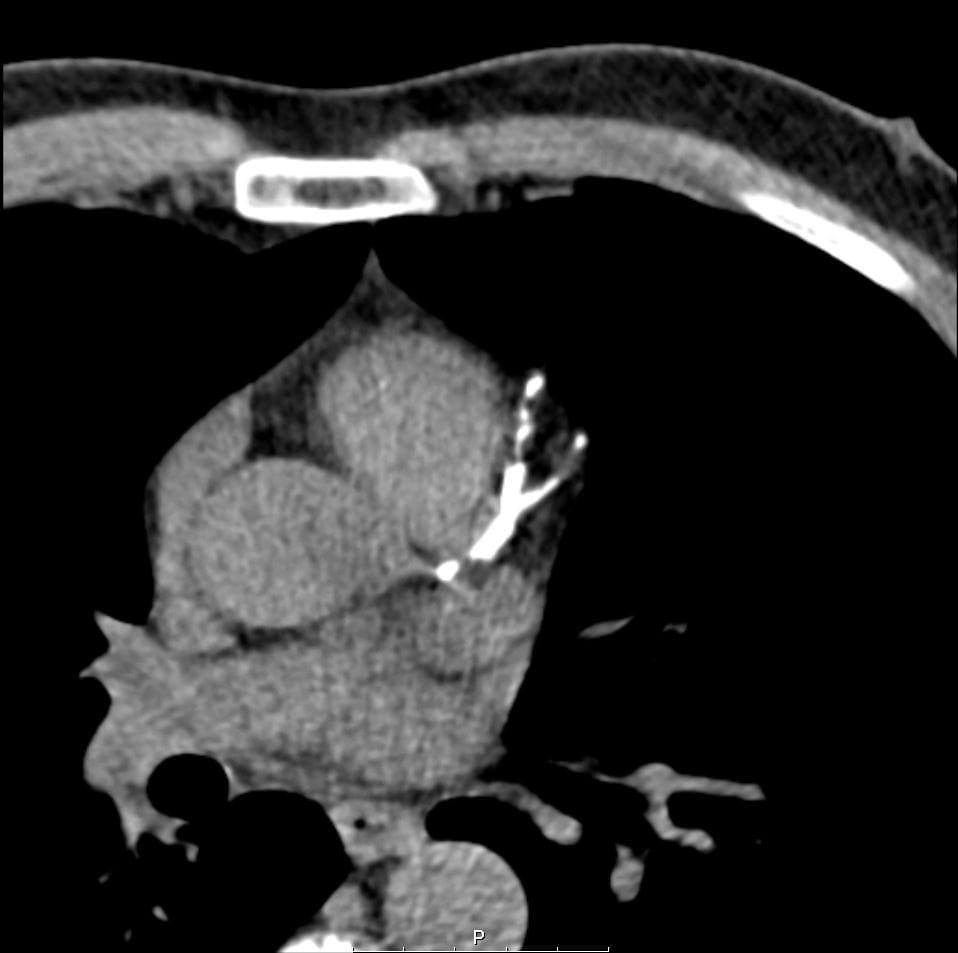

One patient story highlights the potential of CLARIFY to prevent an impending cardiac event. A 56-year-old man had high blood pressure, high cholesterol and a family history of heart disease. He had the opportunity to receive no-charge CAC, which flagged an extremely elevated risk level of 1274.

CACS high risk image CACS high risk image

“Calcium deposits were distributed over all three coronary vessels, including the left main coronary artery,” says Sadeer Al-Kindi, MD, a cardiologist at UH Harrington Heart & Vascular Institute specializing in advanced cardiovascular imaging and an Assistant Professor at the School of Medicine.

The patient underwent a stress test that showed equivocal results and was deemed indeterminate. An elective heart catheterization showed complete occlusion of the left anterior descending artery, left circumflex artery and the end-segment of the right coronary artery.

“Given his extensive blockages, University Hospitals heart surgeons performed coronary artery bypass surgery,” Dr. Al-Kindi says. “The CAC screening alerted us to a risk that might have not been addressed based on symptom presentation, and the patient experienced excellent outcomes.”